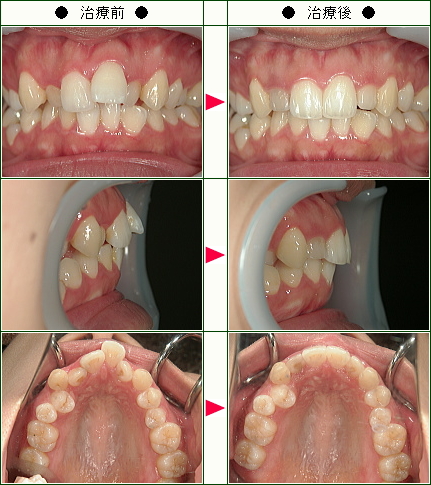

☆歯のデコボコ矯正症例(I様 25歳 女性)